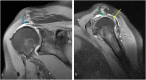

The rotator cuff is a group of four muscles and tendons surrounding the shoulder joint providing it strength and stability. The rotator cuff consists of the subscapularis, supraspinatus, infraspinatus and teres minor. Many shoulder complaints are caused by rotator cuff pathology such as impingement syndrome, tendon tears and other diseases e.g. calcific tendonitis. Diagnosis starts with clinical history and physical examination, after which imaging is often used to help confirm clinical findings depending on the differential diagnosis. The aim of the article is to review the frequently used imaging modalities to assess the rotator cuff and cuff-related disease, specifically focusing on radiography, ultrasonography and magnetic resonance imaging. This article will outline the advantages and disadvantages for each modality and illustrate typical radiological findings of common rotator cuff pathologies.